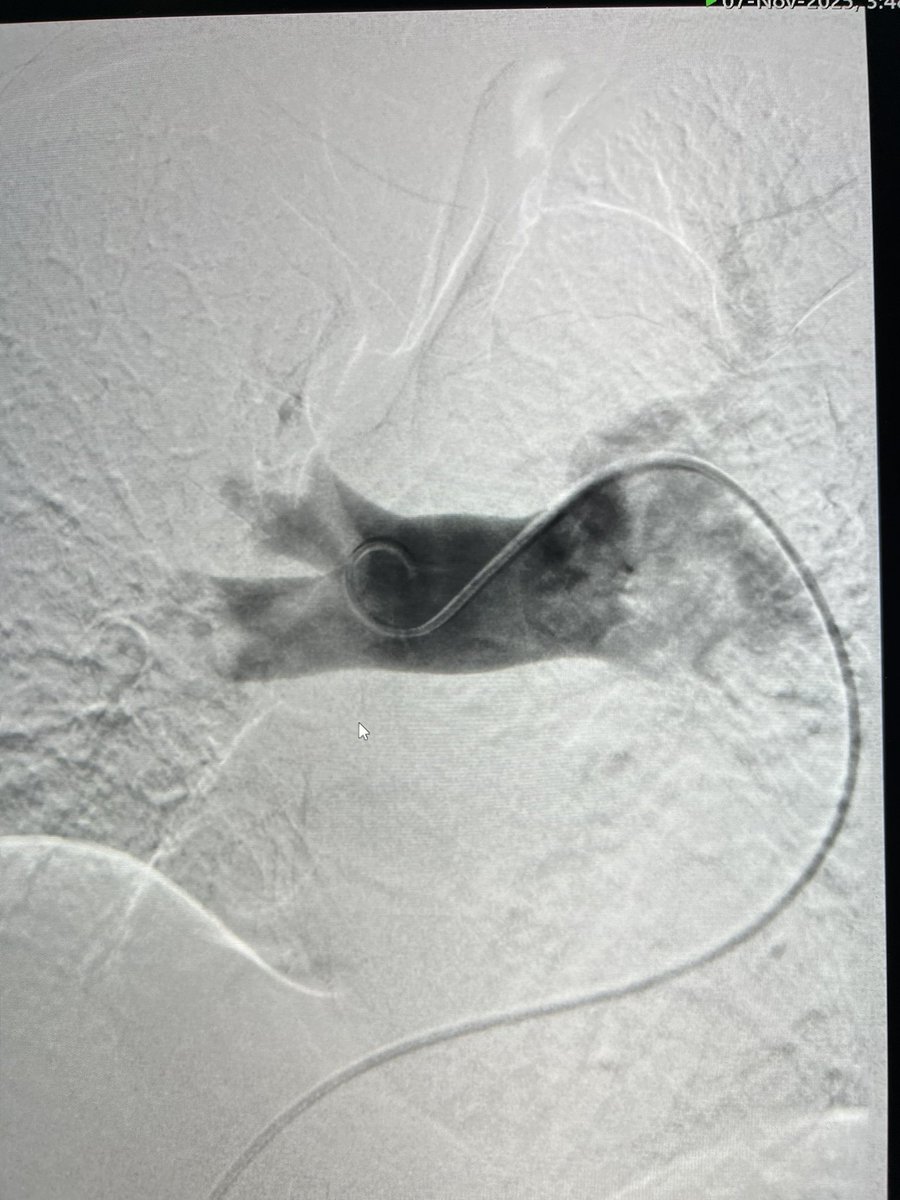

Large volume IVC thrombectomy and mod sed TIPS done same session - patient was able to be discharged and make it to her sons wedding - she fit much better into her dress with no ascites!